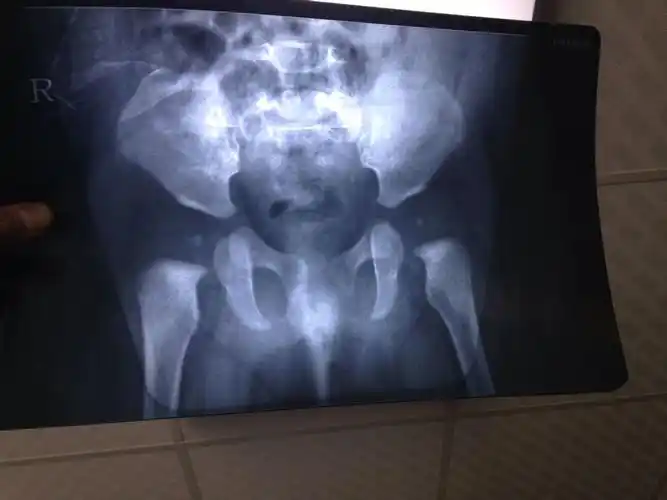

注意宝宝双腿的这些表现,可能是得了这种骨骼病_髋关节

坐标武汉宝宝两岁髋关节发育不良

很想写点什么,纪念自己陪宝宝打怪的这三个月时间重庆对髋关节发育

5个月大宝宝髋关节发育不良

家长提问:四个月大的婴儿髋关节发育不良会对小孩有什么影响?